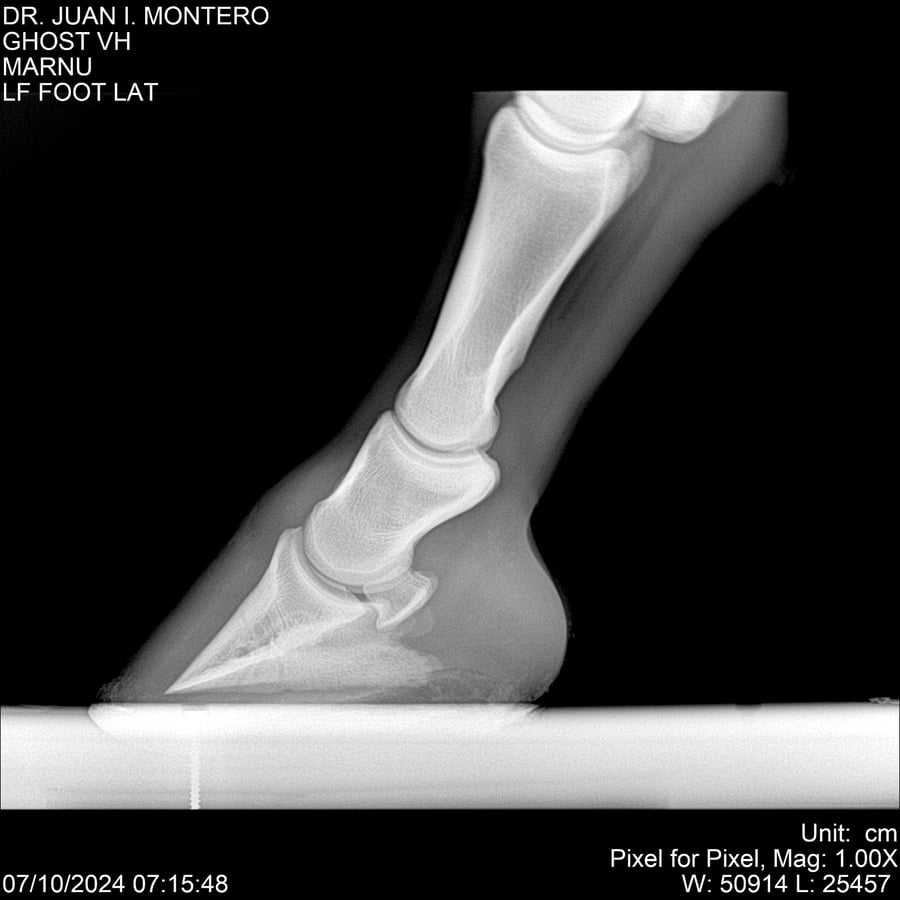

LOTE 15, GHOST VH 🔥 🔥 🔥 Lote Anterior Volver al remate Lote Siguiente Ficha Contacto Montevideo - Ficha del Lote Identificador: #282525 Categoría: Yeguarizos Montevideo - 69 Visualizaciones ClicData Contacto Empresa: Abelenda N. R., Walter Hugo Nombre*: Teléfono* : E-mail* : Mensaje Enviar Registrese gratis Este contenido Exclusivo está disponible sólo para usuarios registrados Ingresar